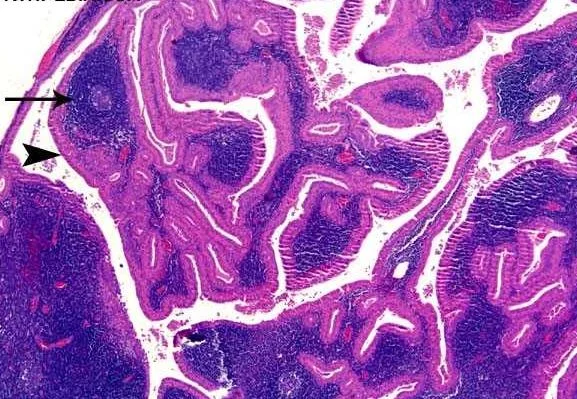

Our patient had a Warthin’s tumor.  This is a benign cystic tumor of the salivary gland which  has mostly lymph-node like stroma.  It was named for Aldred Warthin who first described two cases in 1929.  This is the only benign tumor restricted to the parotid gland. It is the second most common tumor with the first being a pleomorphic adenoma. Smokers are at eight times greater risk than non smokers.

On US there are multiple cystic spaces which are surrounded by epithelial cells.  The epithelium contains lymphoid tissue with germinal center formation.

cystic appearance of a Warthin’s tumor